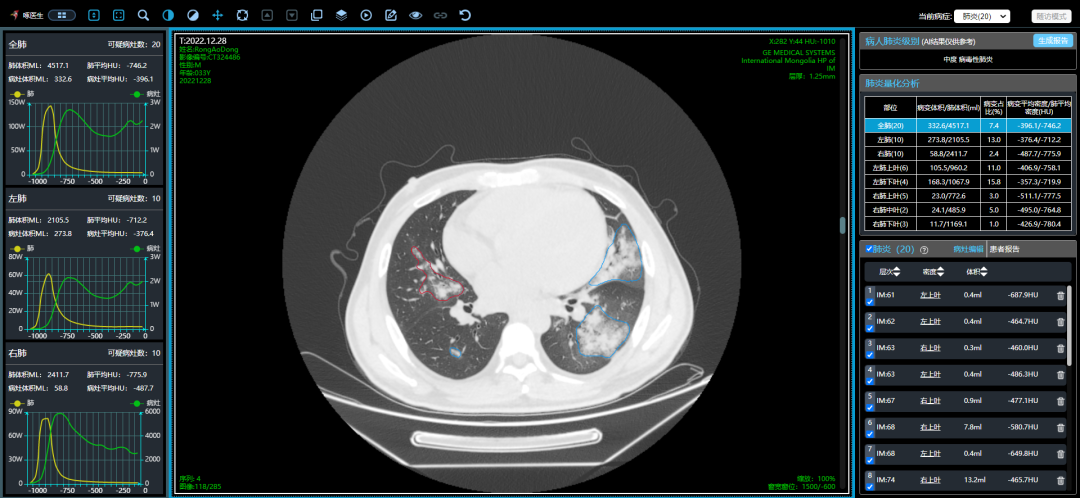

從這3個確診新冠肺炎呈“白肺”病例來看,“白肺”多見于老人、兒童以及帶有基礎(chǔ)病的新冠患者,病灶可發(fā)生在肺內(nèi)任何肺葉,病灶形態(tài)特點(diǎn)也是多樣化,符合病毒性肺炎的影像表現(xiàn)。從影像學(xué)角度出發(fā)重點(diǎn)在于快速評估病情,提升人工讀片的客觀性。 “啄醫(yī)生閱片機(jī)器人??新冠肺炎CT影像輔助分診與評估系統(tǒng)”可以準(zhǔn)確地識別新冠肺炎的典型影像表現(xiàn)如雙肺外周胸膜下多發(fā)的磨玻璃影、小葉間隔增厚或合并鋪路石征等,對于部分患者由于影像表現(xiàn)早于臨床癥狀,更具有早期發(fā)現(xiàn)、早期診斷的優(yōu)勢。